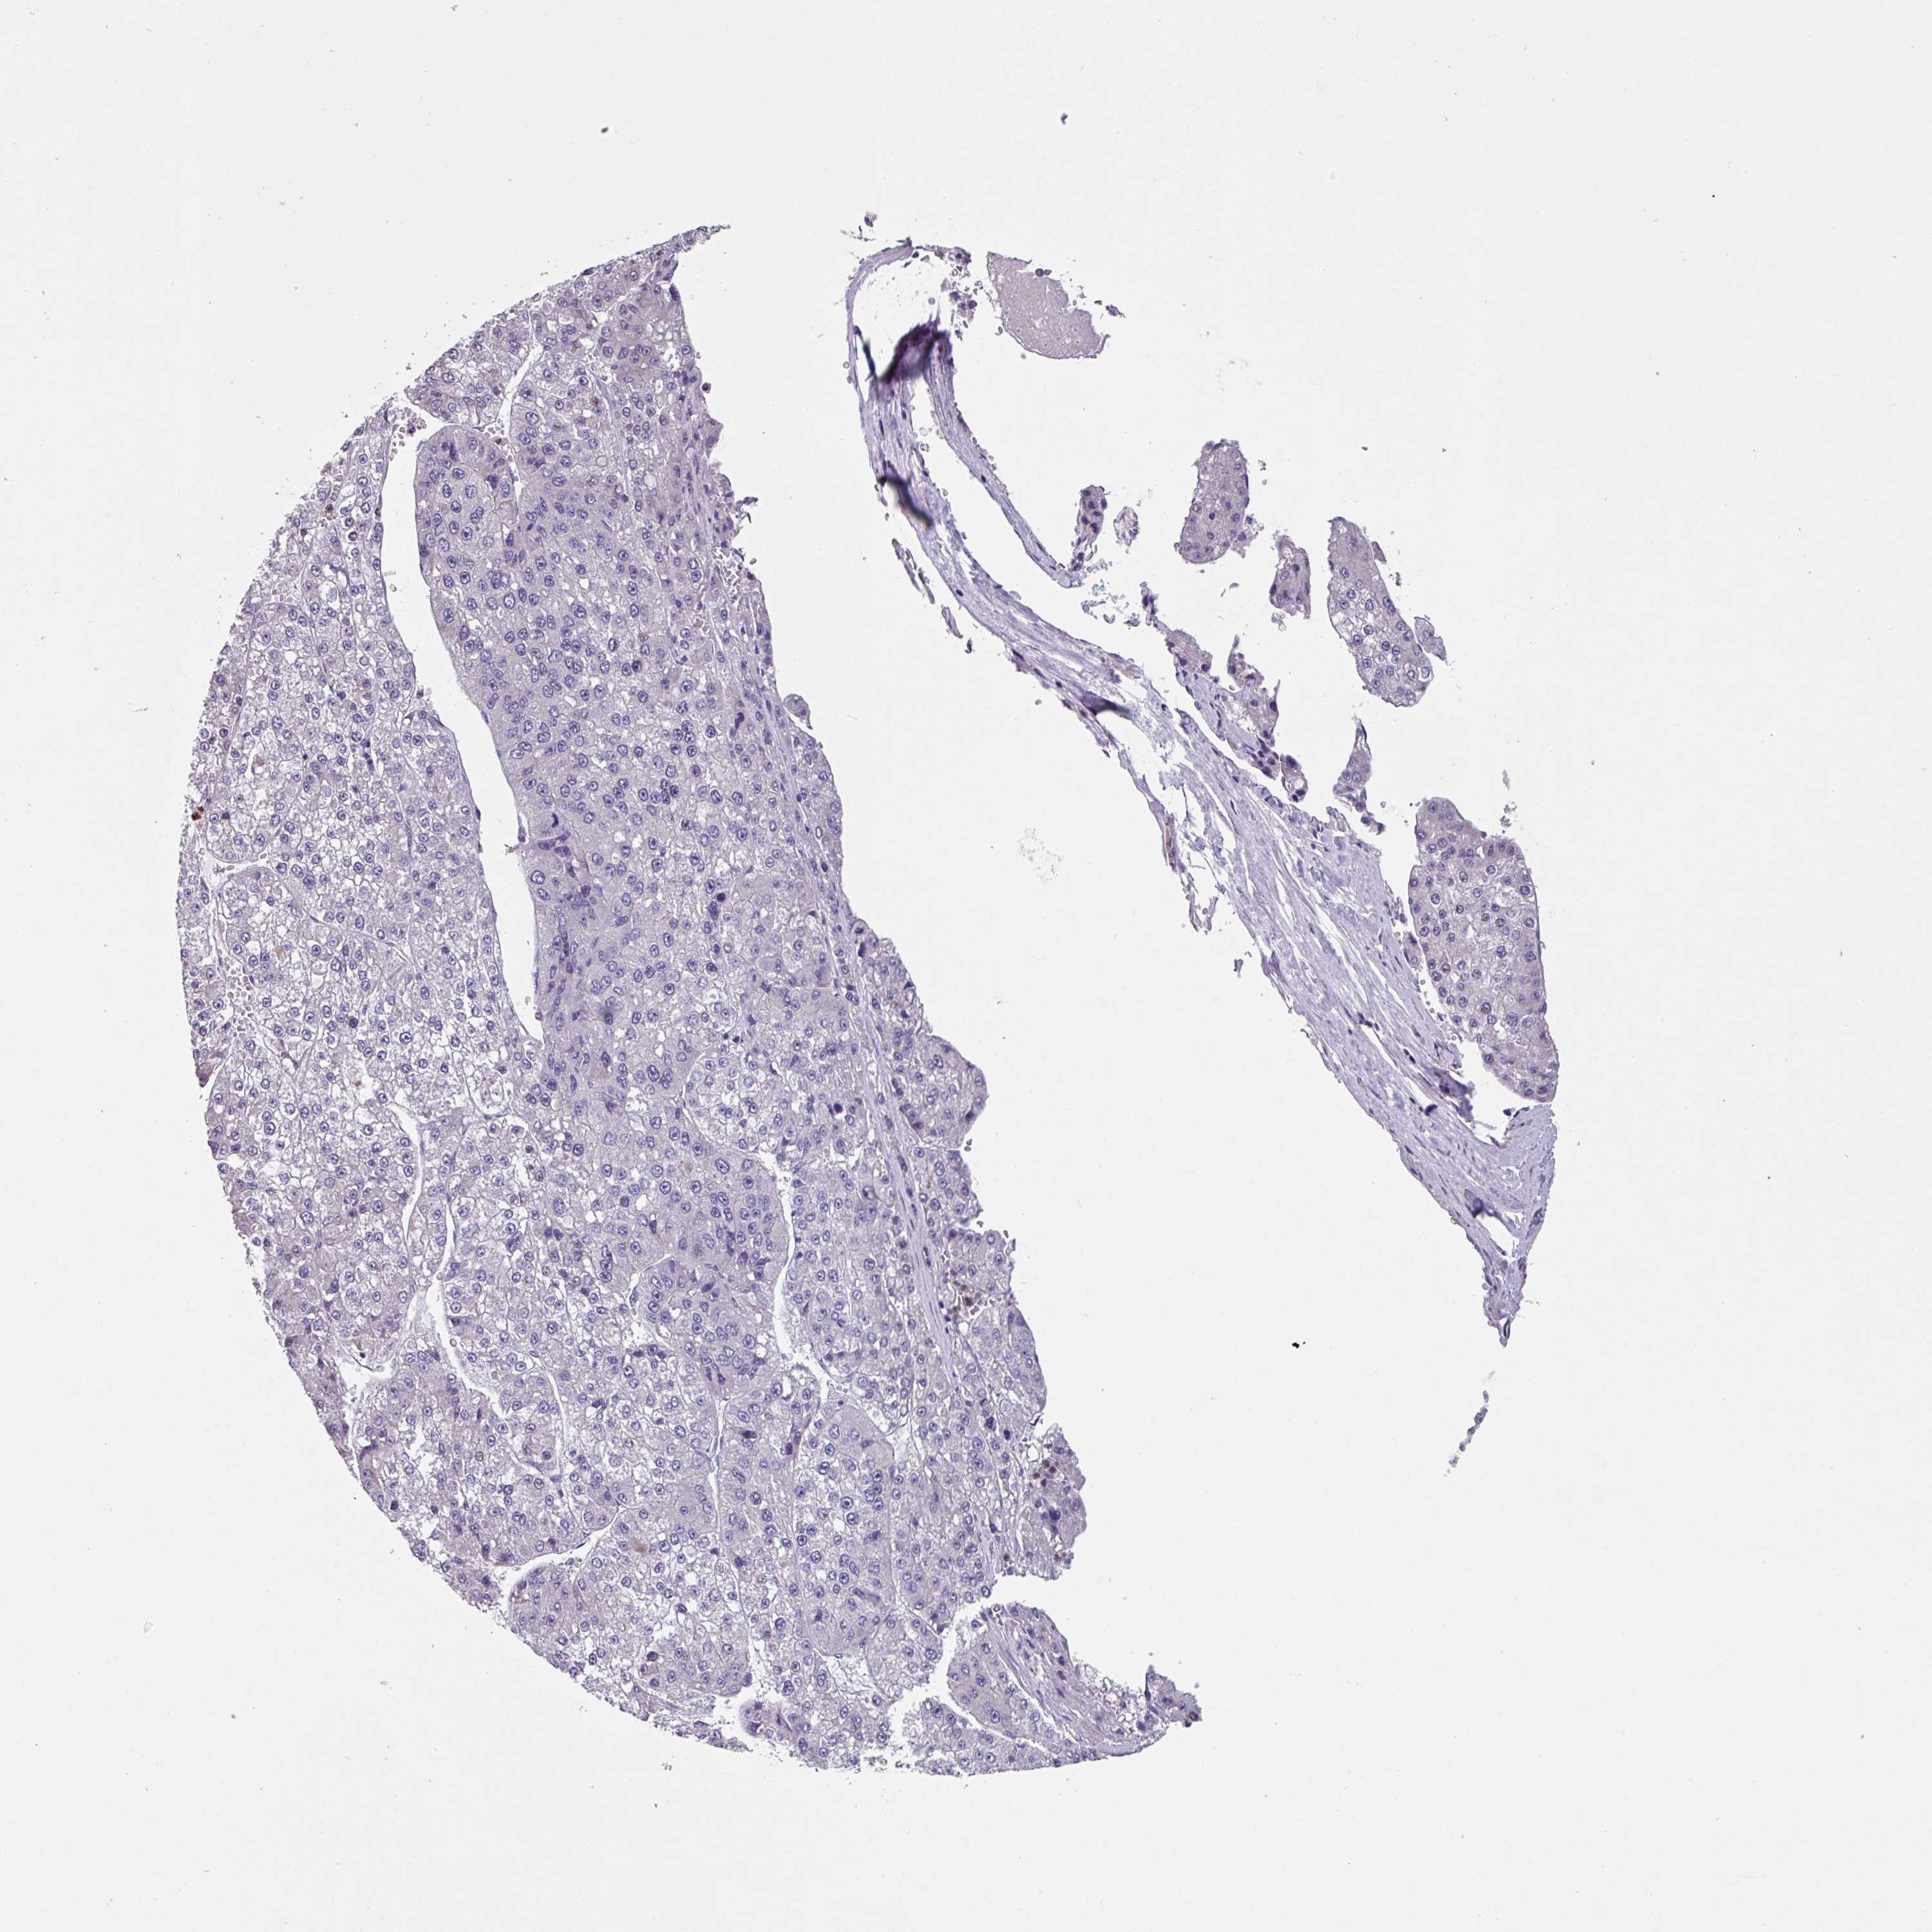

LIVER CANCER - Protein expressioni

A mouse-over function shows sample information and annotation data. Click on an image to view it in a full screen mode. Samples can be filtered based on level of antibody staining by selecting one or several of the following categories: high, medium, low and not detected. The assay and annotation is described here.

Note that samples used for immunohistochemistry by the Human Protein Atlas do not correspond to samples in the TCGA dataset.

Antibody stainingi

Antibody staining in the annotated cell types in the current human tissue is reported as not detected, low, medium, or high, based on conventional immunohistochemistry profiling in selected tissues. This score is based on the combination of the staining intensity and fraction of stained cells.

Each image is clickable and will lead to virtual microscopy that enables deeper exploration of all samples and also displays staining intensity scores, fraction scores and subcellular localization as well as patient and tissue information for each sample.

Antibody HPA053085

Staining

High

Medium

Low

Not detected

Intensity

Strong

Moderate

Weak

Negative

Quantity

>75%

75%-25%

<25%

None

Location

Nuclear

Cytoplasmic/membranous

Cytoplasmic/membranous,nuclear

Cholangiocarcinoma

Carcinoma, Hepatocellular, NOS